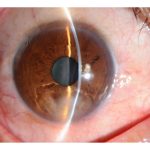

Signs of bacterial keratitis:

▪ conjunctival injection

▪ focal white infiltrates (with epithelial demarcation and underlying stromal inflammation).